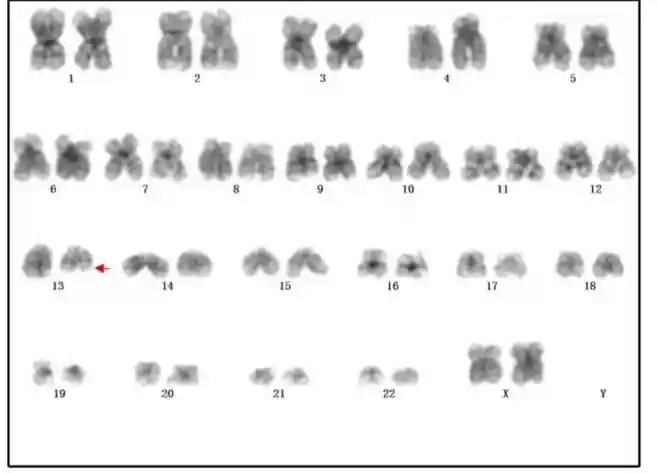

诊断意见:骨髓纤维化,需结合临床及基因学等检查。染色体检查(图6):46,XX,del(13)(q1222)[4]/46,XX[7]。基因检测:CALRTypel阳性,BCR/ABL融合基因、JAK2-V617F、MPL-W515L/K阴性。诊断为原发性骨髓纤维化。

图6染色体核型检查